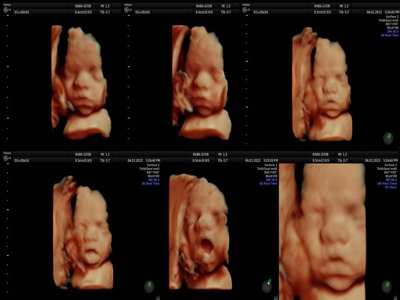

La ecografía 4D HD/5D consiste en la adquisición y presentación continúa de volúmenes. La denominación de la técnica obedece a que hay cuatro dimensiones involucradas: ancho, largo, profundidad y tiempo.

Si bien la Ecografía 4D HD/5D puede realizarse en cualquier etapa del embarazo, recomendamos realizarla entre las semanas 24 a 32 de gestación ya que se pueden observar rasgos bien definidos en el bebe.

Fotografías de ecografías 4D HD/5D

Haga click sobre las imágenes para ampliar